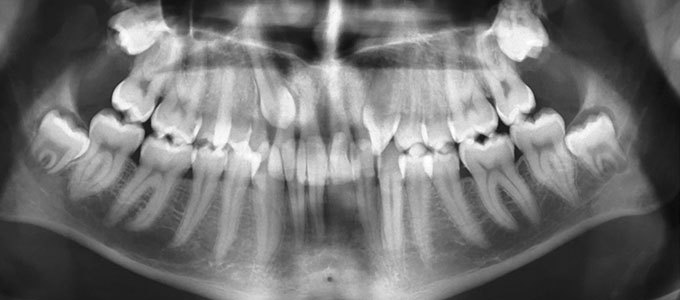

Tratamentul ortodontic nu este o soluție rapidă. Acesta începe întotdeauna cu o examinare minuțioasă a dinților, a buzelor și a întregului aspect facial, sunt necesare radiografii si fotografii de diagnostic. Din aceste informații detaliate medicul ortodont dezvoltă un plan de tratament personalizat.